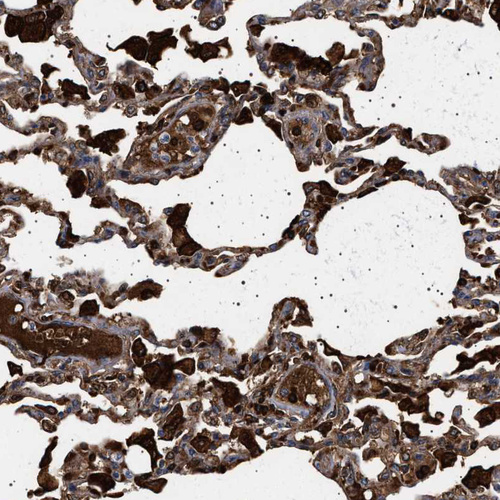

Immunohistochemical staining of human Testis shows strong granular cytoplasmic positivity in Leydig cells and cells in seminiferous ducts.